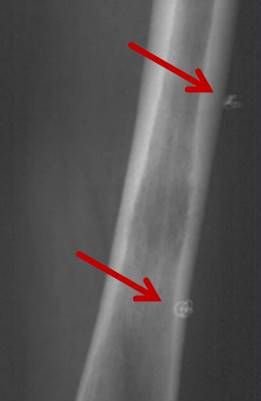

Das Osteoidosteom ist ein gutartiger, jedoch sehr schmerzhafter Knochentumor, der bevorzugt bei jüngeren Patienten auftritt. Die Radiofrequenzablation (RFA) hat sich in den letzten Jahren zu einer zuverlässigen, minimalinvasiven Therapieoption bei der Behandlung des Osteoidosteoms entwickelt und wird seit über 15 Jahren an der Uniklinik Tübingen angewandt.

Abbildung: Osteoidosteom (Pfeil) im Schienbein bei einem jungen Patienten. Unter CT-Bildgebung wird ein spezieller Applikatoren unter CT-Bildgebung in das Osteoidosteom eingebracht. Durch Hitze wird dieses effektiv und dauerhaft zerstört.